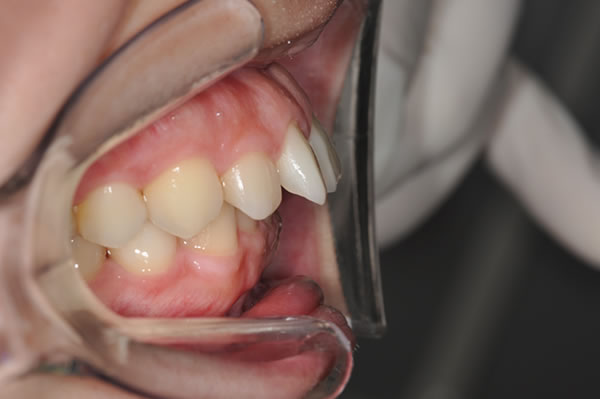

上顎前突症の治療例

上顎前突症(出っ歯)の矯正症例 ケース01

上顎前突症(出っ歯)の矯正症例 ケース02